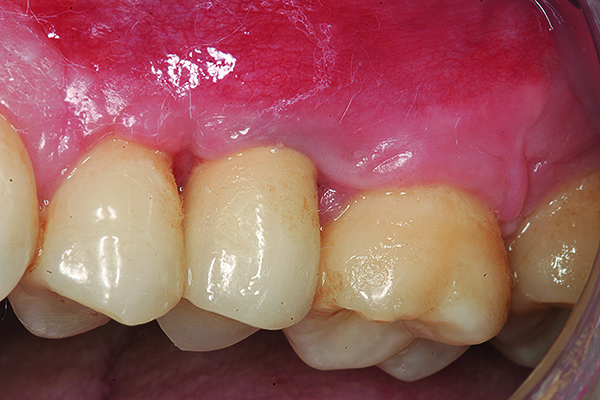

The implant restoration and surrounding soft tissue seen in Fig 3, 5 years following treatment.

Figure 4

Maxillary right lateral incisor implant restoration with severe bone and soft tissue loss is classified a major complication which may not be completely reversible.

Figure 5